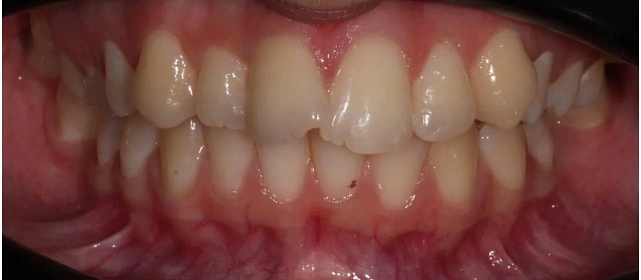

Неровные зубы, неправильное смыкание.

Нарушение соотношения челюстей и неправильное положение зубов — зубные ряды смыкались некорректно, зубы стояли со смещением.

Проблема: В клинику обратилась пациентка — беспокоили неровные зубы и неправильное смыкание. Зубные ряды сходились некорректно, зубы стояли со смещением, что влияло и на внешний вид, и на распределение нагрузки при жевании.

Решение: Поставили элайнеры 3D Smile на обе челюсти. Лечение заняло 4 года и потребовало нескольких последовательных этапов коррекции. Капы менялись каждые 1–2 недели, на контрольных визитах отслеживали прогресс и выдавали новые наборы. Зубы встали в правильное положение, смыкание нормализовалось. Зафиксировали ретейнеры на обе челюсти, изготовили ретенционные капы. Пациентка прошла онлайн-консультацию с ортопедом для оценки дальнейших шагов.